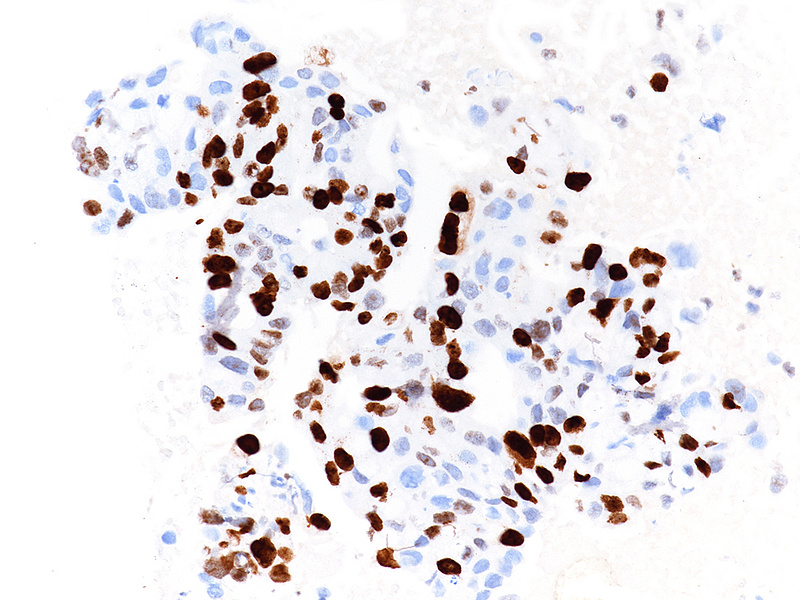

By immunohistochemistry, the tumour cells were strongly and diffusely positive for CK7 (Panel F), focally positive also for p40 (Panel G) and CK20 (not shown). Ki67 labelling index confirmed the suspected high proliferation rate, estimated between 40-50% (Panel H). The immunohistochemical screening for DNA mismatch repair (MMR) deficiency showed no loss of protein expression. A final diagnosis of poorly (to undifferentiated) adenocarcinoma of the pancreas with squamous differentiation (consistent with adenosquamous carcinoma) was made.